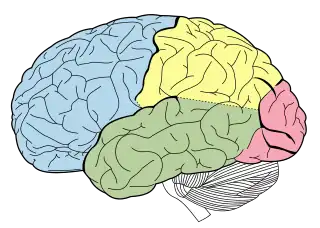

| Visión lateral de los lóbulos cerebrales. |